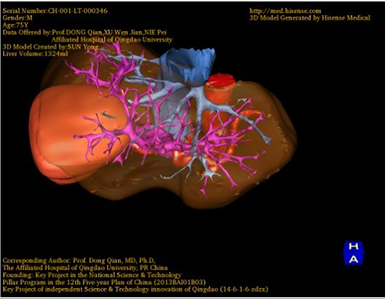

胆管细胞癌-CH-001-LT-000346

一般情况:CH-001-LT-000346,74岁男性患者。

将0.625mm双源薄层CT资料的静脉期和动脉期Dicom格式文件导入海信CAS系统。

通过调节窗宽窗位调整CT序号,对肿瘤,肝实质,胆囊,下腔静脉,肿瘤,肝动脉、门静脉及肝静脉等进行三维重建;系统自动计算肿瘤体积和肝脏体积。(图2—截图1---后链接截图2)

模拟手术操作,自动计算切除肿瘤体积。肝脏体积为1324ml,肿瘤体积为286.1ml,肿瘤体积为肝脏体积的21.6%,通过比对70-80岁正常肝脏体积为1118.08±190.14ml,通过术前模拟手术,精准判断切除后剩余肝脏体积能耐受,避免肝衰竭发生。术前手术方案的规划。

术前三维重建:

重建图片